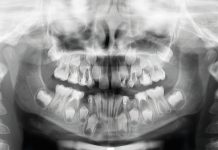

Presso il reparto di Chirurgia Orale dell’Ospedale San Raffaele di Milano si è presentato alla nostra attenzione un paziente maschio di 18 anni, con anamnesi medica negativa. All’esame obiettivo intraorale si è evidenziato un settore edentulo nel secondo quadrante con un evidente deficit osseo orizzontale (figura 1-2). Si è proceduto poi all’esecuzione di una ortopantomografia (OPT) che ha confermato l’agenesia degli elementi 22 e 23 e di una TC cone-beam (CBCT) al fine di esaminare, attraverso le cross-section, il reale spessore della cresta atrofica residua.